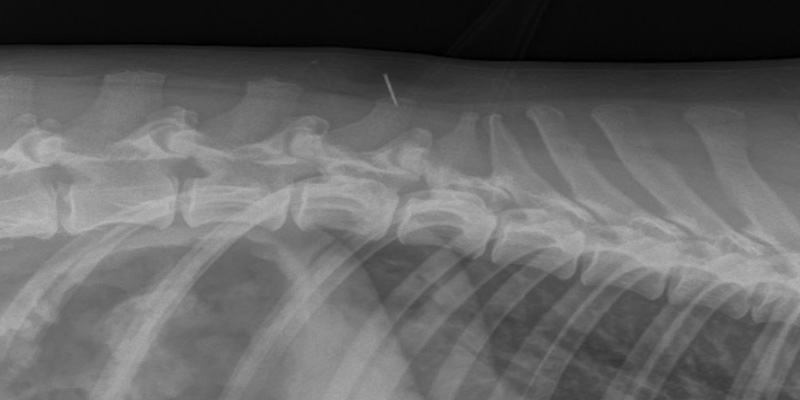

In February, Elsa appeared suddenly painful and restless. She was examined and mid-spine was found to be focal in her discomfort. She was given pain relief (buprenorphine and meloxicam) and advised to adhere to strict rest. The following day, she was experiencing ataxia and upon re-examination delayed hind-limb proprioception was identified. Radiographs showed spondylosis (Figure 1) throughout the lumbar region as well as moderate to severe bilateral hip dysplasia. It was advised rest and analgesia was to continue. Elsa was also prescribed gabapentin and previcox.

Figure 1